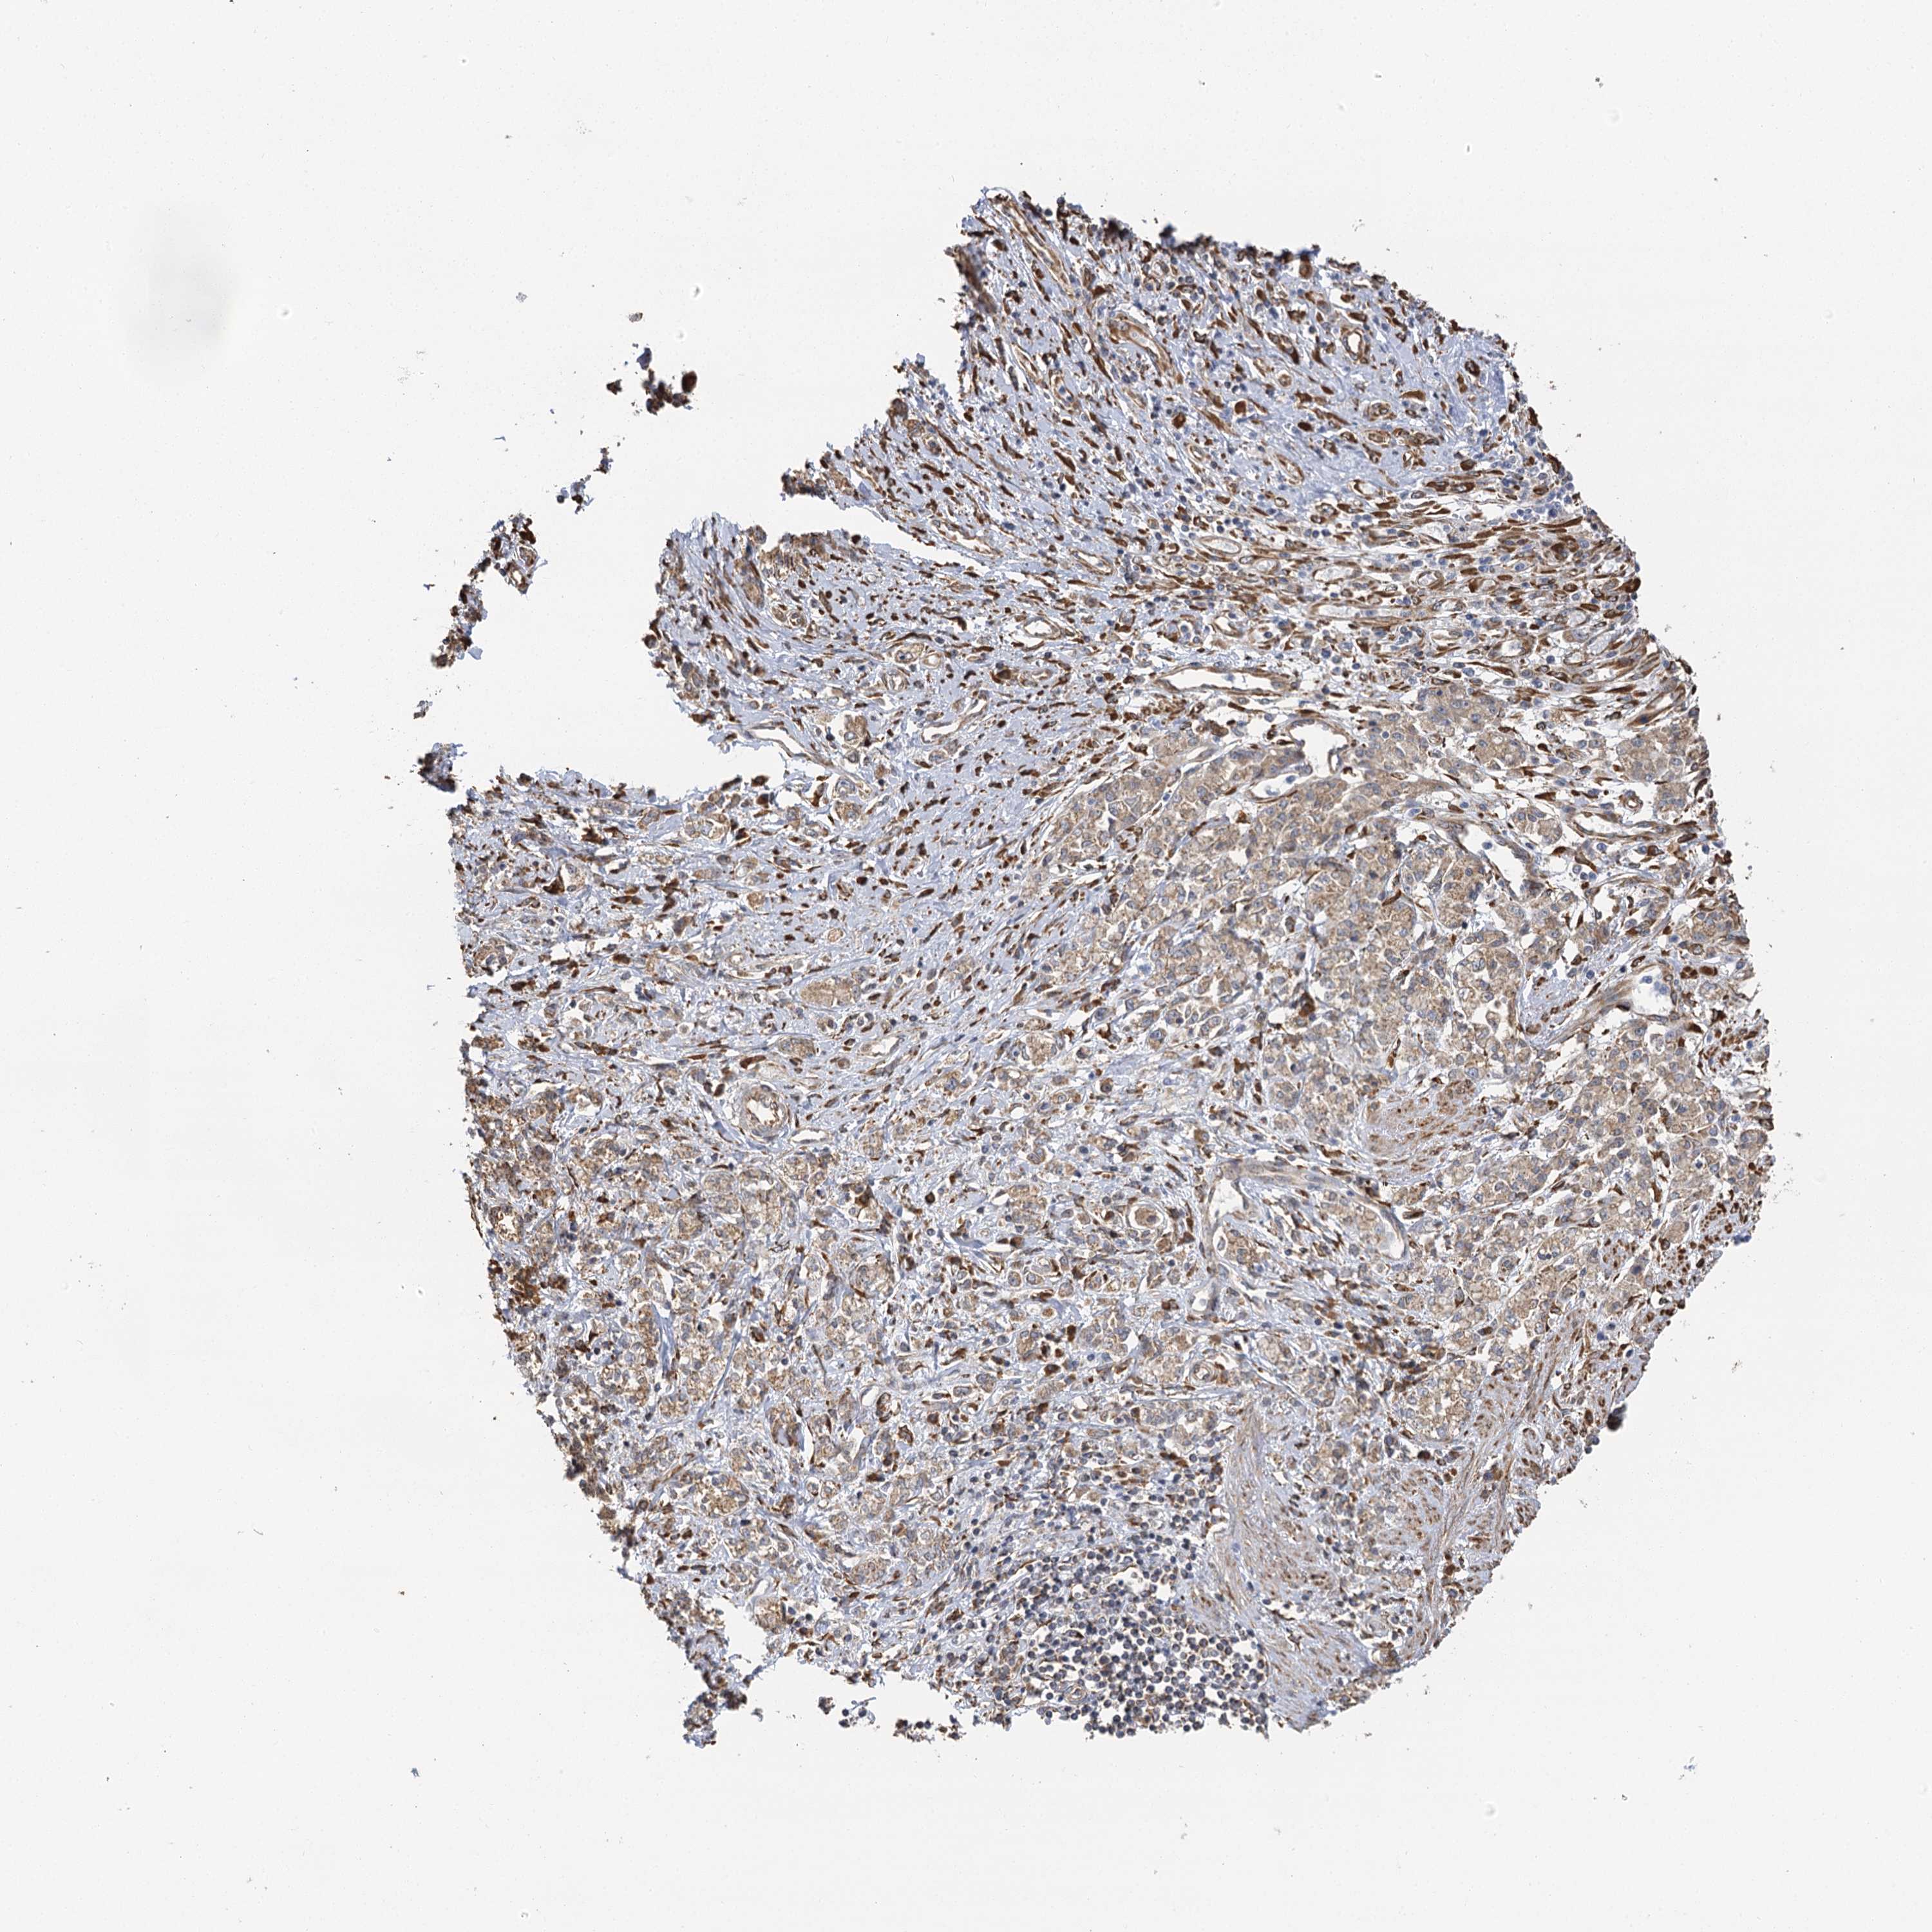

STOMACH CANCER - Protein expressioni

A mouse-over function shows sample information and annotation data. Click on an image to view it in a full screen mode. Samples can be filtered based on level of antibody staining by selecting one or several of the following categories: high, medium, low and not detected. The assay and annotation is described here.

Note that samples used for immunohistochemistry by the Human Protein Atlas do not correspond to samples in the TCGA dataset.

Antibody stainingi

Antibody staining in the annotated cell types in the current human tissue is reported as not detected, low, medium, or high, based on conventional immunohistochemistry profiling in selected tissues. This score is based on the combination of the staining intensity and fraction of stained cells.

Each image is clickable and will lead to virtual microscopy that enables deeper exploration of all samples and also displays staining intensity scores, fraction scores and subcellular localization as well as patient and tissue information for each sample.

Antibody HPA013162

Antibody HPA036652

Antibody CAB032830

Staining

High

Medium

Low

Not detected

Intensity

Strong

Moderate

Weak

Negative

Quantity

>75%

75%-25%

<25%

None

Location

Nuclear

Cytoplasmic/membranous

Cytoplasmic/membranous,nuclear

Adenocarcinoma, NOS

Adenocarcinoma, High grade